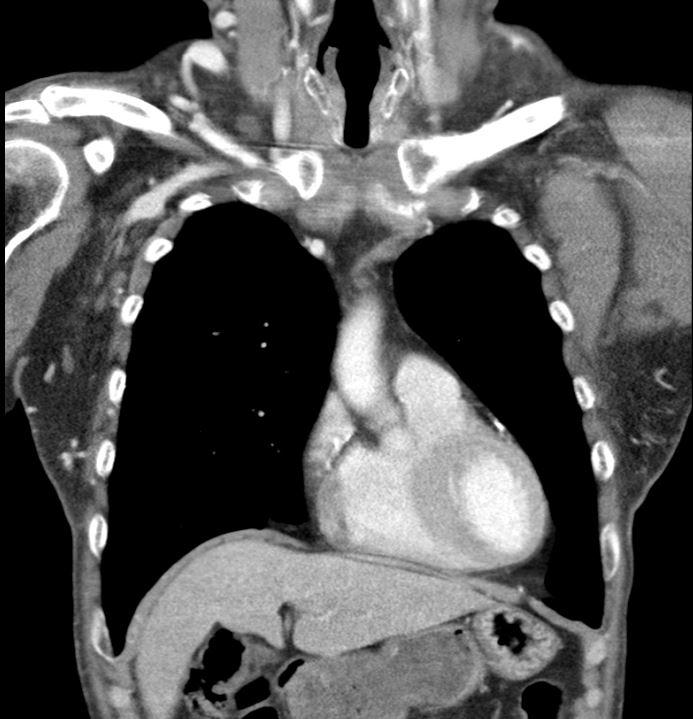

A 53-year-old man with type 2 diabetes, hypertension, COPD, and end-stage renal disease on hemodialysis presented with progressive facial swelling for one month. Vital signs were stable. Examination revealed a high-pitched voice, facial and bilateral upper limb swelling, and prominent chest wall venous engorgement. Chest CT showed bilateral brachiocephalic vein obstruction with multiple collaterals, consistent with superior vena cava (SVC) syndrome.

Relevant Test Results Prior to Catheterization

Chest CT revealed chronic thrombosis of the left brachiocephalic vein and a diminutive right brachiocephalic vein with multiple collateral channels, findings consistent with superior vena cava (SVC) syndrome secondary to chronic central venous obstruction.